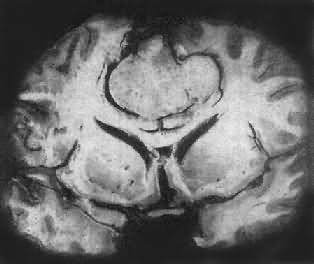

图16-26 髓母细胞瘤 瘤细胞较小,着色深,密集排列,有菊形团形成 髓母细胞瘤恶性程度高,预后差。 (三)脑膜瘤 脑膜瘤(meningioma)可来源于脑膜的各组成成分如蛛网膜细胞,纤维母细胞或血管,其中多数来源于蛛网膜颗粒中的蛛网膜细胞。本瘤大多生长缓慢,良性类型可完全无症状,在70岁以上老人的尸检中,发现无症状的脑膜瘤不在少数,无症状脑膜瘤占颅内肿瘤的14%。脑膜瘤患者多为40~50岁中年人,女性较男性多。 肿瘤的好发部位与蛛网膜颗粒所在部位相同,常见于上矢状窦旁大脑镰两侧,蝶骨嵴,嗅沟,小脑脑桥角;在脊髓则以胸段为多见,一般颅内脑膜瘤较脊髓脑膜瘤多2倍。 肉眼观,肿瘤呈球形,分叶状或不规则形,质实或硬,边界清楚,周围脑组织受压成凹陷切迹(图16-27)。少数肿瘤呈斑块状覆盖较广泛区域,甚至整个脑半球,称为斑块型脑膜瘤。肿瘤质地硬,切面灰白色,呈颗粒状、条索旋涡状,有的质地似砂砾样,乃由于有多量砂粒体存在。

图16-28 脑膜瘤 瘤细胞为圆形或多角形,作旋涡状排列 (4)血管母细胞型:肿瘤细胞丰富,胞浆模糊,胞核椭圆,多排列在毛细血管旁,并有较多的网状纤维。 各型脑膜瘤中均可有不同程度的出血、钙化,有些并有黄色瘤细胞、软骨、骨、黑色素及粘液样变。 大多数脑膜瘤为良性,瘤细胞可引起邻近颅骨的骨质增生,或肿瘤浸润,但不引起广泛播散或转移,也不侵入邻近的神经组织。一般手术后复发率可达15%,其中血管母细胞型有复发和播散倾向,预后较差。少数脑膜瘤细胞间变明显,与梭形细胞肉瘤难以区分,可发生颅外转移,主要累及肺及淋巴结。